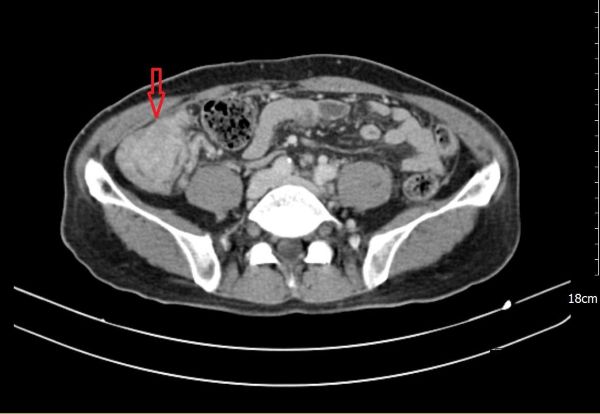

【視傳媒記者吉雄世高雄報導】66 歲的陳先生自去年八、九月起,陸續出現全身倦怠、食慾不振、腹脹與腹瀉等情形,短短兩個月內體重減少約6公斤,因身體不適至義大癌治療醫院一般外科趙頌慈醫師門診求診,經檢查後發現,血紅素偏低並合併營養狀況不佳,影像檢查發現罹患多發性結腸癌,且腫瘤已擴散至腹腔,對病人與家屬而言是噩耗。

經義大癌治療醫院跨科團隊整體評估後,依其臨床狀況規劃分階段治療,先安排化學治療合併標靶藥物。治療過程中,陳先生雖出現輕微疲倦,但腹脹、腹瀉等不適症狀逐漸緩解,整體身體狀況趨於穩定。

在腫瘤反應與身體條件允許下,醫療團隊進一步評估後,建議接受「腹腔高壓氣霧化學治療(PIPAC)」。此為以腹腔鏡進行的微創治療方式,將化療藥物於高壓環境中霧化,使藥物能較均勻分佈於腹腔內,作為部分腹膜癌病人之治療選項之一。陳先生完成一個療程、共三次「腹腔高壓氣霧化學治療(PIPAC)」 後,臨床症狀與檢查結果顯示病情獲得控制,相關評估指標亦呈現改善趨勢。